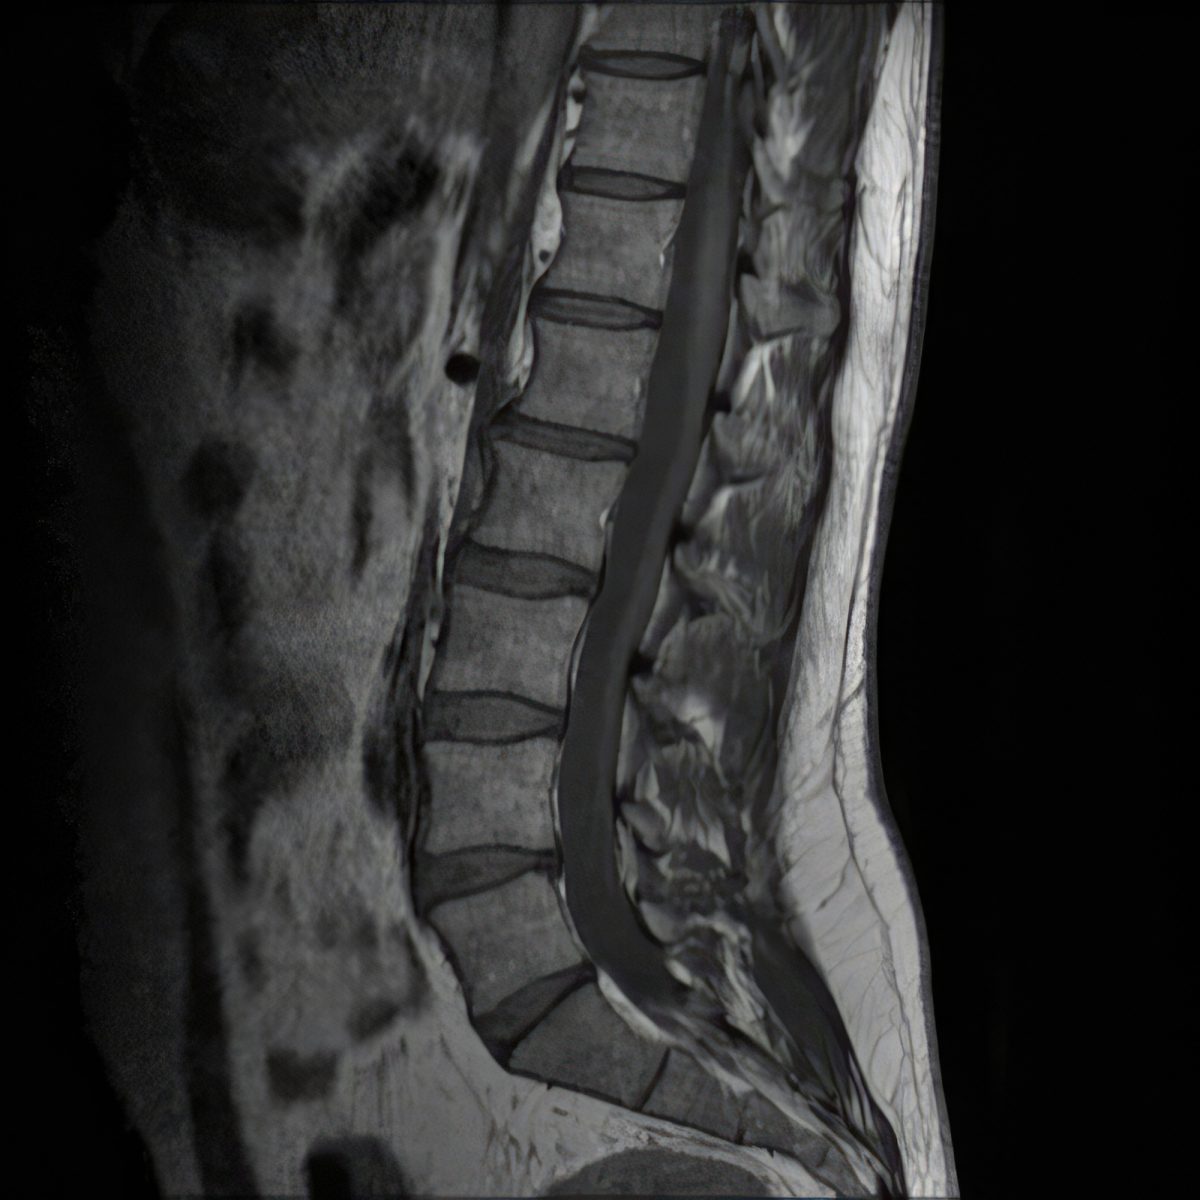

La catégorie « Chirurgie lombaire » regroupe l’ensemble de nos articles et pages dédiés aux pathologies et aux traitements chirurgicaux du bas du dos. Vous y trouverez des informations claires sur les affections courantes (hernie discale, arthrose facettaire, sténose lombaire, spondylolisthésis, fractures, discopathies), les différentes techniques opératoires disponibles (microchirurgie, endoscopie, fusion lombaire, prothèse discale, stabilisation dynamique), leurs indications respectives, le déroulement des interventions et les étapes de la récupération. Cette section a pour objectif d’accompagner chaque patient dans sa compréhension des options de chirurgie lombaire, qu’il s’agisse de soulager la douleur, de restaurer la mobilité ou de traiter une instabilité, en présentant les innovations les plus récentes et les conseils pour optimiser le retour à la vie active.

- MRI